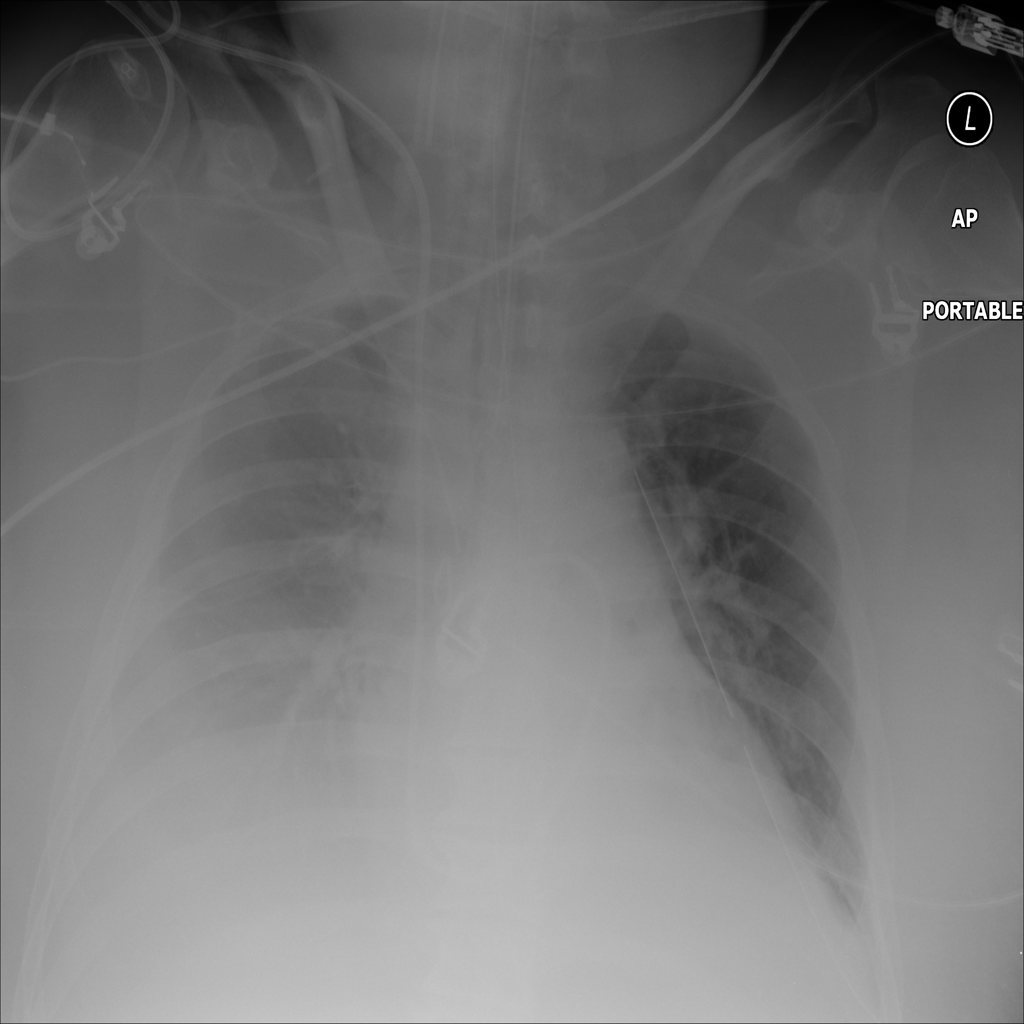

PAT-64EB · IMG-015Consolidation

PAT-64EB · IMG-015

AP